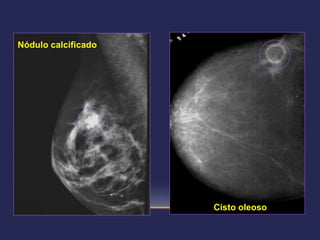

 Categoria 2: achados benignos – seguimento: rotina

   cistos simples                    calcificações vasculares

   linfonodos intramamários          calcificações cutâneas

   próteses                          calcificações com centro lucente

   nódulo calcificado                calcificações de doença

   nódulo com densidade de            secretória

gordura (lipoma,                  calcificações tipo “leite de

fibroadenolipoma)                  cálcio”

   cisto oleoso (esteatonecrose)     calcificações redondas (> 0,5

   nódulos que provam ser cistos      mm de diâmetro)

simples após ultra-sonografia     calcificações de fios de sutura

   cicatriz pós-cirúrgica estável

   prováveis fibroadenomas

   sem modificações em estudos

sucessivos                                      Atlas BI-RADS (ACR) 4ª edição

Nódulo calcificado

Cisto oleoso